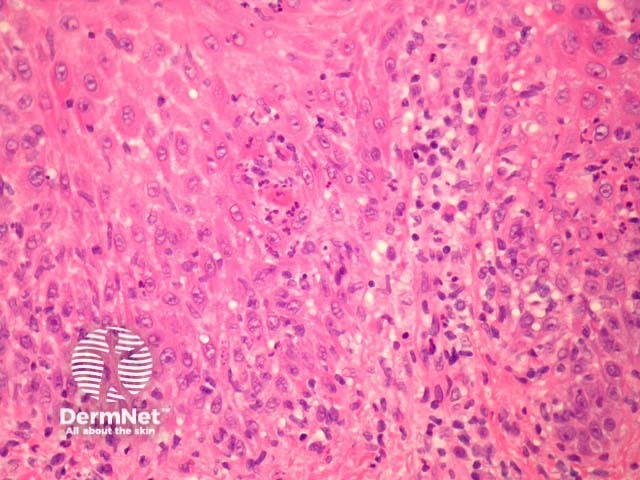

Secondary syphilis exhibits considerable histopathologic variability and may be easily misinterpreted. The epidermis is often involved and shows a psoriasiform hyperplasia with superficial neutrophils (figure 2). There is also a lichenoid tissue reaction, epidermal apoptosis and exocytosis of neutrophils (figure 3). The dermis shows a superficial and deep chronic infiltrate which may resemble the changes of primary syphilis. There are numerous plasma cells in about 1/3 of cases and often endothelial swelling (figure 1).

Figure 3